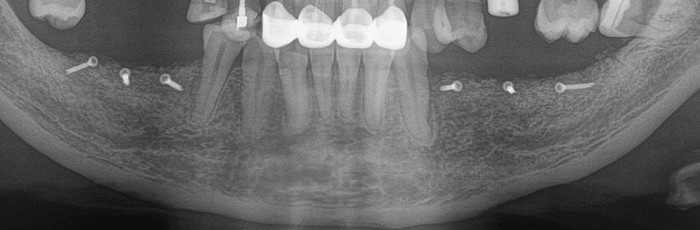

Контрольный рентгеновский снимок:

А как стало на промежуточном этапе:

Согласитесь, выглядит очень даже неплохо, если опустить цвет.